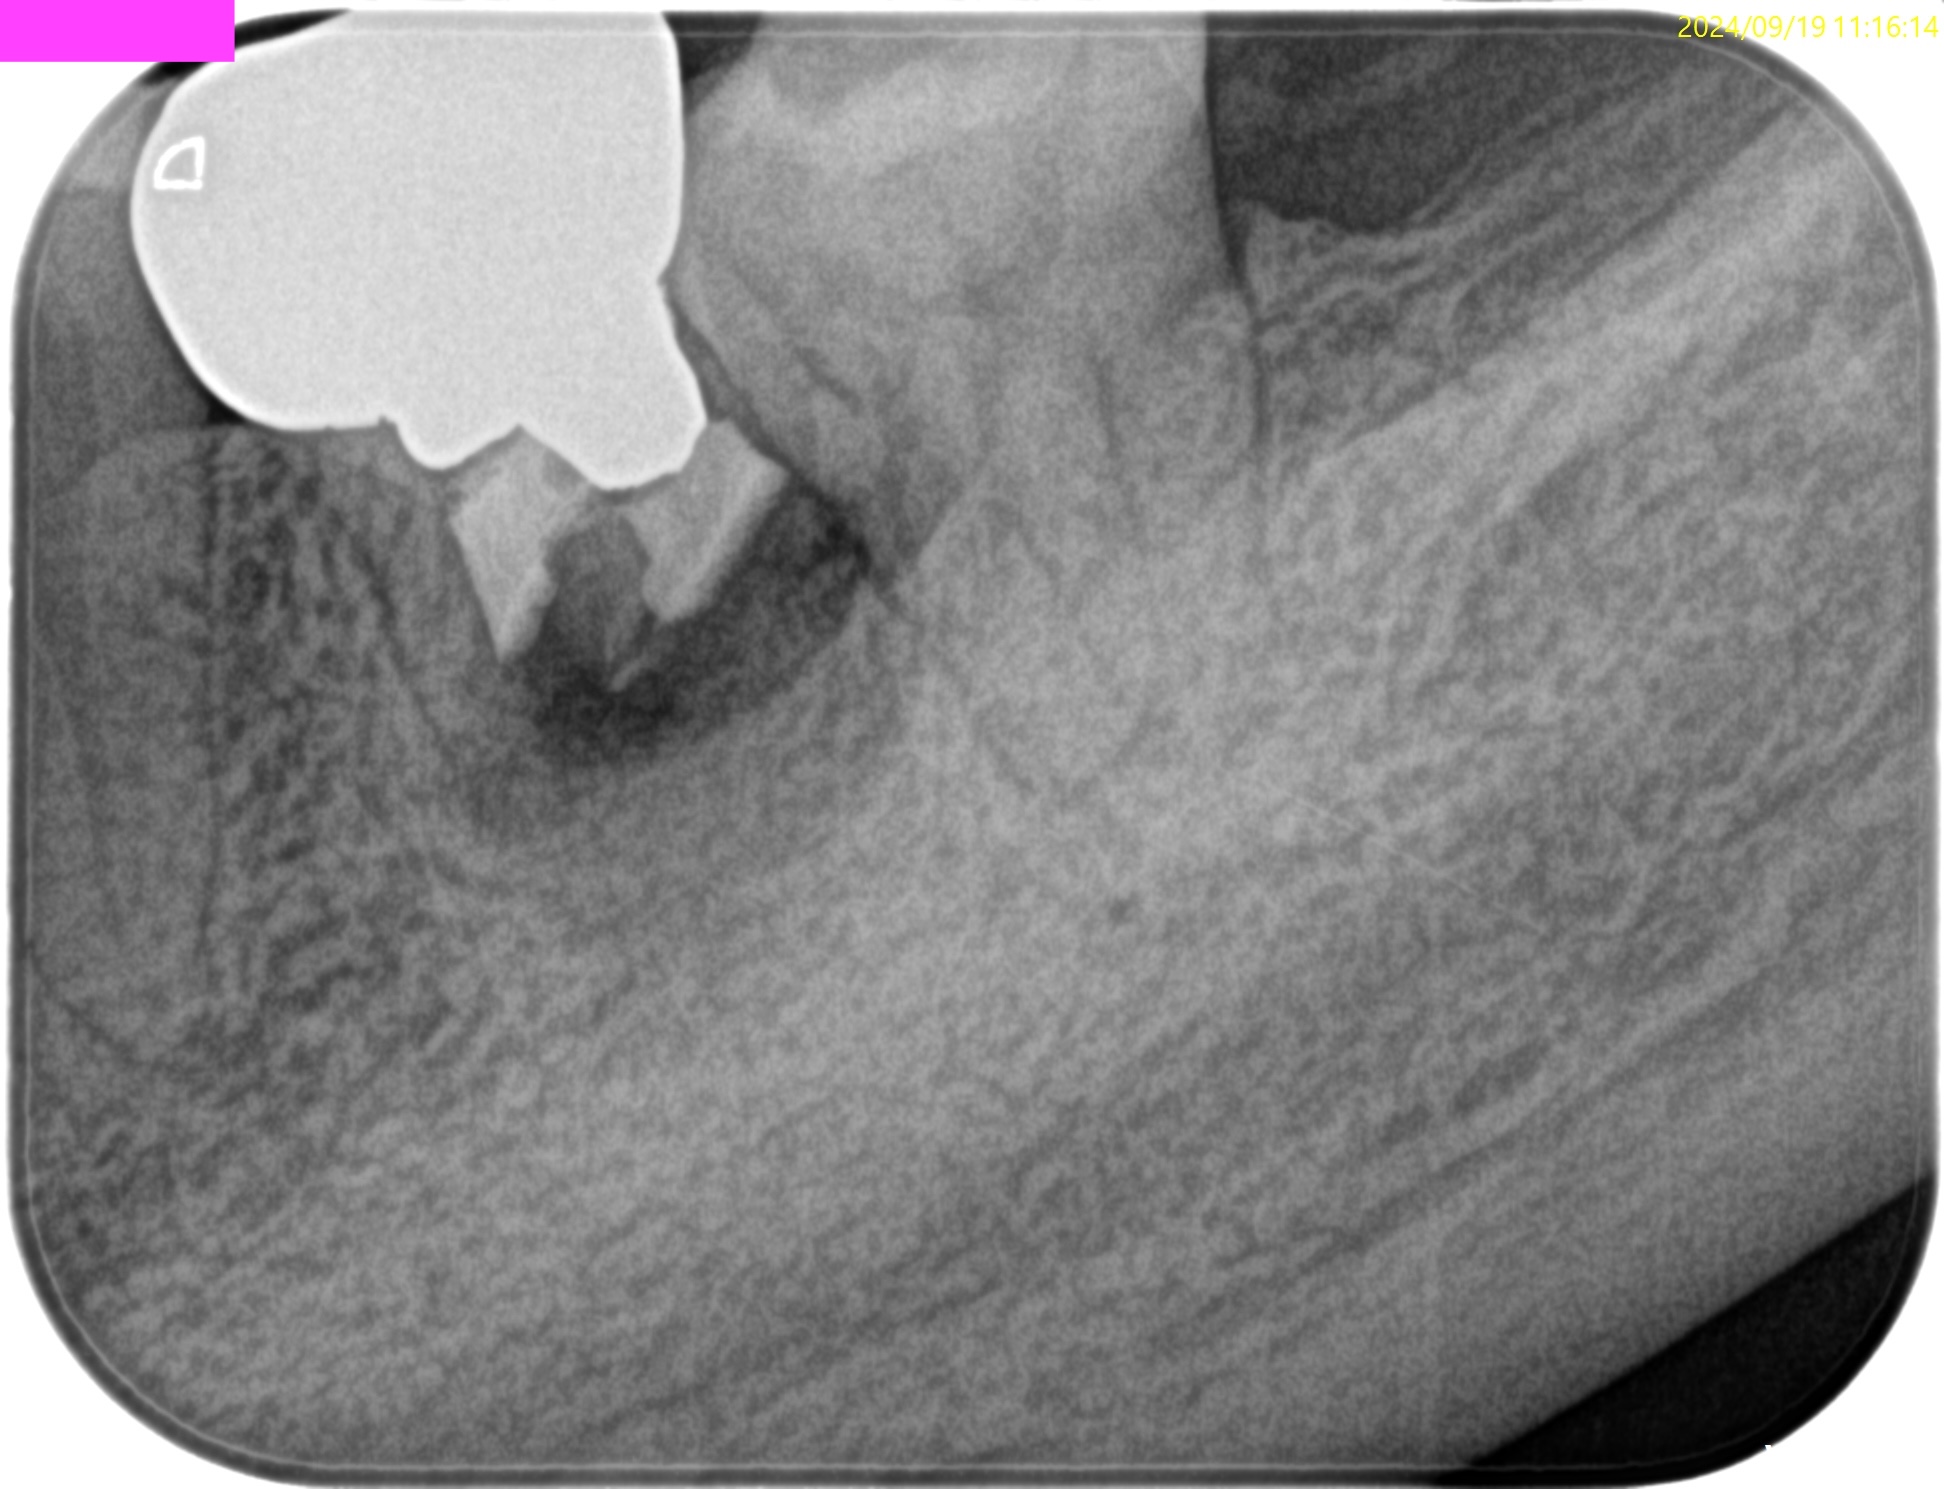

PA(2024.9.12)

CBCT(2024.9.12)